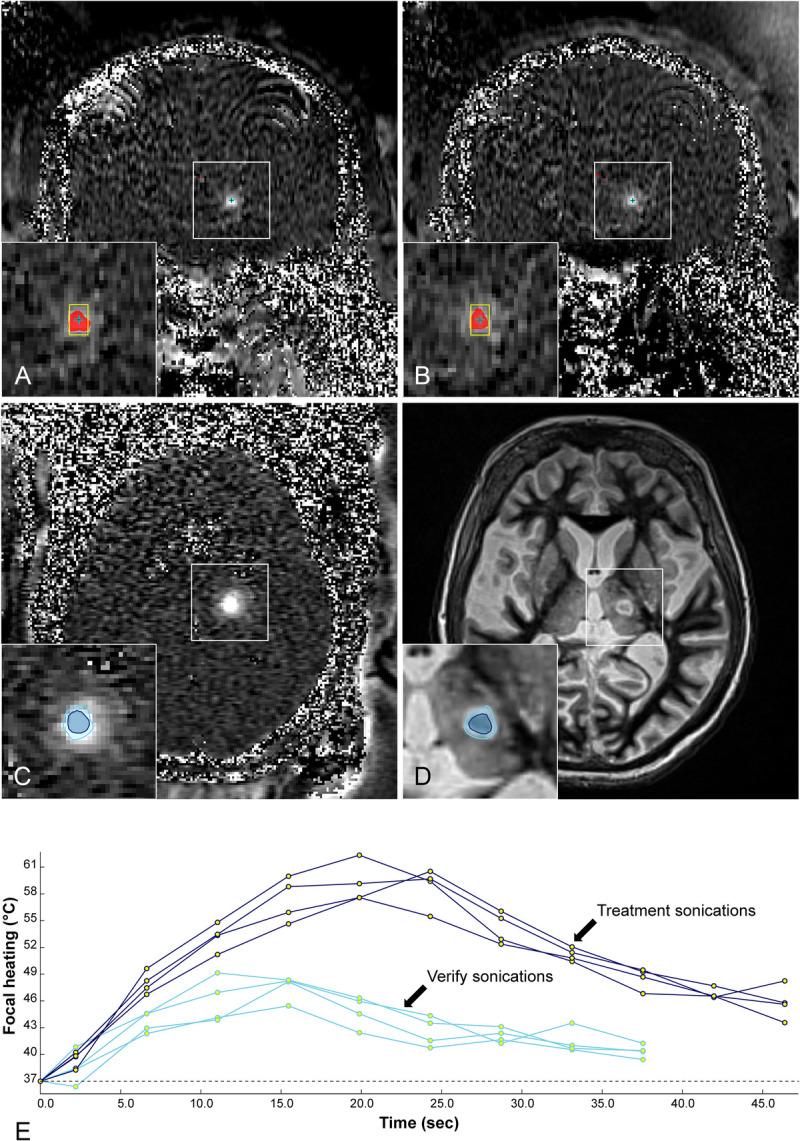

聚焦超声:非侵入性图像引导治疗。

Focused Ultrasound: Noninvasive Image-Guided Therapy.

Invasive open surgery used to be compulsory to access tumor mass to perform excision or resection. Development of minimally invasive laparoscopic procedures followed, as well as catheter-based approaches, such as stenting, endovascular surgery, chemoembolization, brachytherapy, which minimize side effects and reduce the risks to patients. Completely noninvasive procedures bring further benefits in terms of reducing risk, procedure time, recovery time, potential of infection, or other side effects. Focusing ultrasound waves from the outside of the body specifically at the disease site has proven to be a safe noninvasive approach to localized ablative hyperthermia, mechanical ablation, and targeted drug delivery. Focused ultrasound as a medical intervention was proposed decades ago, but it only became feasible to plan, guide, monitor, and control the treatment procedures with advanced radiological imaging capabilities. The purpose of this review is to describe the imaging capabilities and approaches to perform these tasks, with the emphasis on magnetic resonance imaging and ultrasound. Some procedures already are in clinical practice, with more at the clinical trial stage. Imaging is fully integrated in the workflow and includes the following: (1) planning, with definition of the target regions and adjacent organs at risk; (2) real-time treatment monitoring via thermometry imaging, cavitation feedback, and motion control, to assure targeting and safety to adjacent normal tissues; and (3) evaluation of treatment efficacy, via assessment of ablation and physiological parameters, such as blood supply. This review also focuses on sonosensitive microparticles and nanoparticles, such as microbubbles injected in the bloodstream. They enable ultrasound energy deposition down to the microvascular level, induce vascular inflammation and shutdown, accelerate clot dissolution, and perform targeted drug delivery interventions, including focal gene delivery. Especially exciting is the ability to perform noninvasive drug delivery via opening of the blood-brain barrier at the desired areas within the brain. Overall, focused ultrasound under image guidance is rapidly developing, to become a choice noninvasive interventional radiology tool to treat disease and cure patients.

过去,为了切除肿瘤块,侵入性开放手术是必须进行的。随后出现了微创腹腔镜手术以及基于导管的治疗方法,如支架置入、血管内手术、化疗栓塞、近距离放射治疗,这些方法可将副作用降至最低并降低患者风险。完全无创的手术在降低风险、手术时间、恢复时间、感染可能性或其他副作用方面带来了更多益处。将体外的聚焦超声波专门作用于疾病部位已被证明是一种安全的无创方法,可用于局部消融热疗、机械消融和靶向药物递送。聚焦超声作为一种医学干预手段在数十年前就已被提出,但只有借助先进的放射成像能力,才能够对治疗过程进行规划、引导、监测和控制。本综述的目的是描述执行这些任务的成像能力和方法,重点是磁共振成像和超声。一些手术已经应用于临床实践,更多的仍处于临床试验阶段。成像完全融入工作流程,包括以下内容:(1)规划,确定目标区域和相邻的危险器官;(2)通过温度成像、空化反馈和运动控制进行实时治疗监测,以确保对相邻正常组织的靶向性和安全性;(3)通过评估消融和生理参数(如血液供应)来评估治疗效果。本综述还关注了对超声敏感的微颗粒和纳米颗粒,如注入血液中的微泡。它们能够将超声能量沉积至微血管水平,引发血管炎症和闭塞,加速血栓溶解,并进行靶向药物递送干预,包括局部基因递送。特别令人兴奋的是能够在大脑内的期望区域通过打开血脑屏障进行无创药物递送。总体而言,图像引导下的聚焦超声正在迅速发展,有望成为治疗疾病和治愈患者的首选无创介入放射学工具。